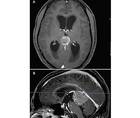

Hearing Loss Associated With Hydrocephalus

Jason A. Ellis, MD; Benjamin W. Y. Lo, MDJason A. Ellis, MD; Benjamin W. Y. Lo, MD - Imaging & Testing